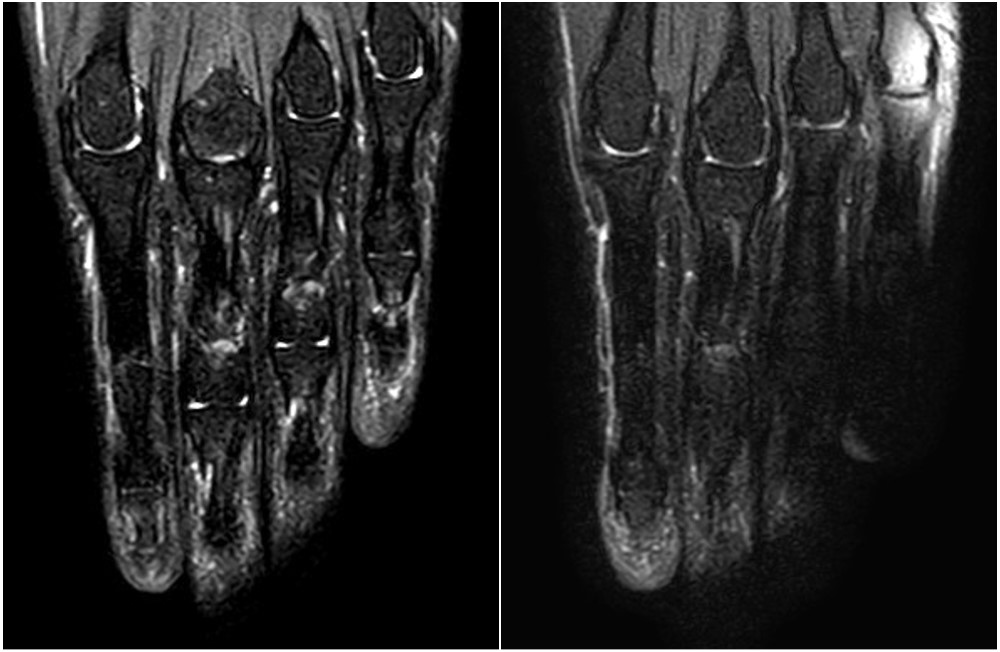

対象部位をできるだけ装置のアイソセンター(磁場中心)に配置することは、B₀/B₁ の不均一性を減らす上で非常に効果的です。Fig.1に対象部位がセンター配置とオフセンター配置の画像の違いを表示します。

センター配置の画像では、指の各側縁でも脂肪抑制が均一にかかっておりコントラストは良好です。一方、オフセンター配置になると、装置端側で脂肪残存や水抑制による信号低下が見られることがあります。これは、周波数選択的脂肪抑制法がB₀および B₁の不均一に敏感なためであり、周波数のズレが脂肪信号の抑制不良や水信号の偽抑制を生み出す要因となります1)。また、患者さんの背中側にクッションをおいて体勢を斜めにすることで対象をよりセンターに配置することができます(Fig.2)。